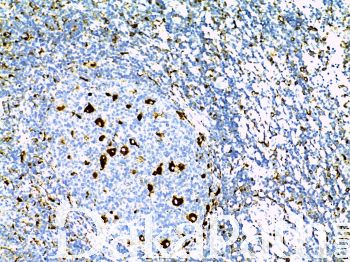

CD68

KP1:分子量为 110kDa 的糖蛋白,与溶酶体颗粒有关。标记巨噬细胞、外周血的单核细胞、骨髓前体细胞和外周血粒细胞,比 PG-M1 克隆广谱;PG-M1:主要用于标记巨噬细胞,组织细胞及其肿瘤,还可与反应性淋巴结中的浆细胞性 T 细胞反应; G 不与粒细胞及其前体细胞反应。

信号定位: 胞浆

表达广泛,特异性差,主要用于组织细胞及其肿瘤的诊断。